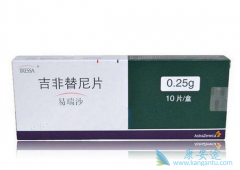

11 月 4 日,JCO 公布 NEJ009 研究结果,旨在评估 EGFR TKI 联合化疗对比 TKI 在 EGFR 突变进展期 非小细胞肺癌(NSCLC)患者中的疗效[1]。和 吉非替尼 单药相比,吉非替尼联合卡铂+培美曲塞显著改善 EGFR 突变患者的 PFS 和 OS,毒性可以接受,再次验证 ...